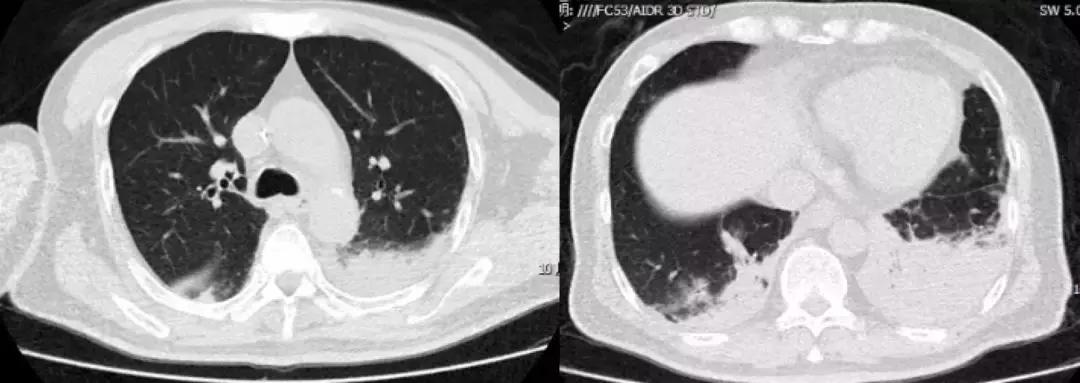

男,67岁,急性病程;发病前有旅游病史;主诉:发热、干咳伴呼吸困难2天,加重1天;查体:体温38.3℃,心率96次/分, 呼吸35次/分,血压98/63mmHg,SpO2 88%(FiO20.37),急性病容,呼吸急促,左肺呼吸音粗,右下肺呼吸音减弱,双下肺可闻及湿啰音;肺部CT示双下肺渗出、实变影,动脉血气分析提示I型呼吸衰竭。

2017-9-26

2017-9-29

支气管镜检查示

双侧气管黏膜充血,可见大量脓黄痰,左下肺基底段灌注生理盐水50ml,回收20ml,送检细菌和真菌涂片、培养;7项呼吸道病原体;EB病毒核酸、巨细胞病毒核酸;抗酸杆菌涂片及染色、结核分枝杆菌鉴定及药敏。最终结果回报:H1N1和金黄色葡萄球菌(MSSA)。降级抗生素为阿莫西林克拉维酸钾联合奥司他韦抗病毒治疗,患者症状好转出院。

经验教训

甲型流感病毒感染后可能出现继发细菌(肺炎链球菌、金黄色葡萄球菌、流感嗜血杆菌等)和曲霉感染,一定注意病原检测,不要过度依赖于强大的抗细菌药物。